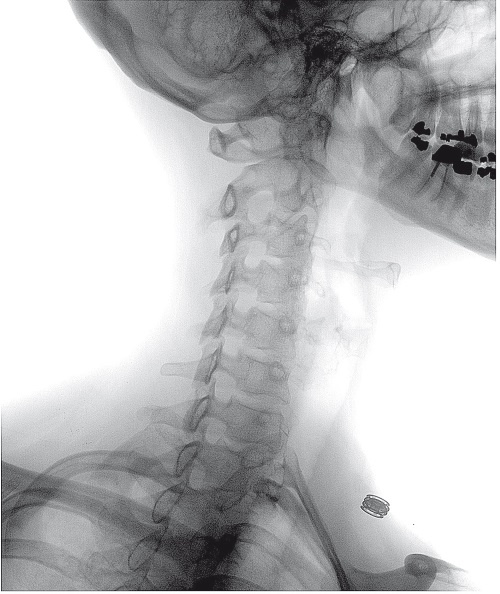

Иллюстрация к книге — Ни кошелька, ни жизни. Нетрадиционная медицина под следствием [i_014.jpg]

Хиропрактики, обычно лечащие проблемы с шеей или спиной с помощью манипуляций на позвоночнике, заняли столь прочное место в системе здравоохранения, что многие читатели, вероятно, даже удивились, увидев этот метод включенным в книгу о нетрадиционной медицине. Ведь многие обычные врачи рекомендуют своим больным обратиться к хиропрактику, а программы страхования, как правило, покрывают подобные процедуры. Это особенно актуально для Америки, где хиропрактиков больше всего и на лечение у них ежегодно тратится около 10 миллиардов долларов. Хиропрактика – не просто официальная часть американской системы здравоохранения, она продолжает набирать популярность: с 1970 по 1990 год число практикующих специалистов утроилось, а в 2002 году в Северной Америке их насчитывалось шестьдесят тысяч. Ожидалось, что к 2010 году их количество еще удвоится, тогда как обычных врачей станет больше всего на 16 %.